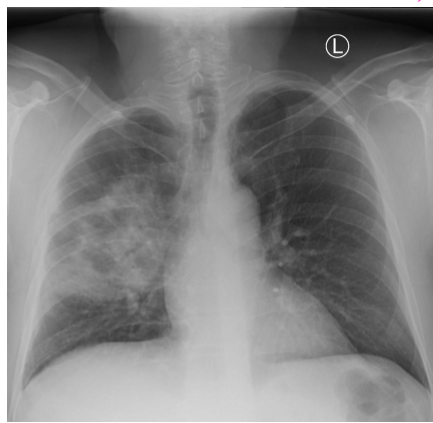

whats the dx?

pleural effusion

COPD